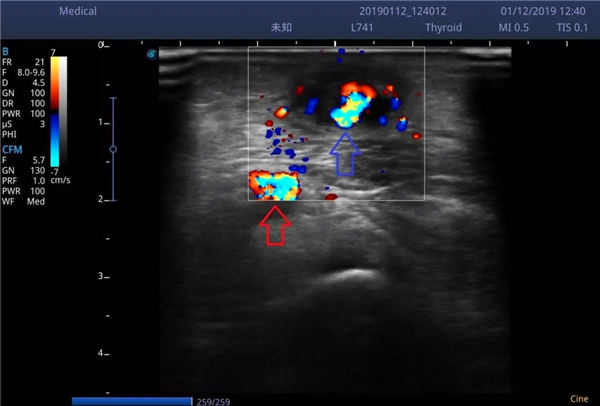

谭老先生和老伴赶到燕化医院一检查,果不其然是桡动脉贵要静脉内瘘闭塞了。如图,超声下闭塞的贵要静脉,完全没有彩色血流。

术后超声显示(如下图):桡动脉(红色箭头)血流通畅,贵要静脉(蓝色箭头)内可见少量彩色血流,但仍有大量血栓,而且这点血流量尚不足以进行透析治疗。